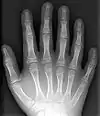

| 患有埃利偉氏症候群的病人,可見他的兩手都是多指畸形及手指很短。 | |

多出來的手指或腳趾一般都只是一細小的軟組織,有時會有骨頭但沒有關節,很少會是完整結構的。額外的手指或腳趾一般是在尺骨那一面(即接近尾指)長出,很少會在橈骨(即拇指)那面,在中間三指間長出則極為罕見。這三種畸形分別稱為軸後多指畸形、中央多指畸形及軸前多指畸形。它很多時會在原有的指上長出,很少會像正常的手指般在手腕長出。

多指畸形,或多趾畸形,是一種涉及額外的手指或腳趾的先天畸形。